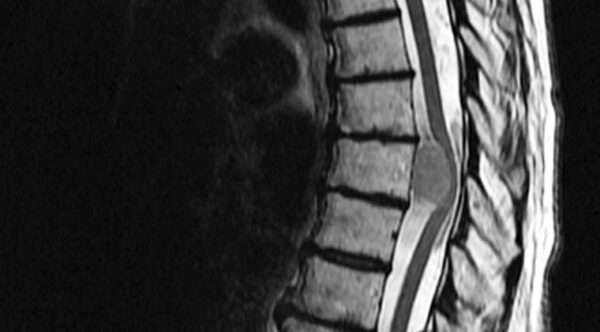

Tumores espinales primarios y metastásicos

Los tumores espinales representan un pequeño porcentaje de todos los tumores del sistema nervioso central, pero su impacto es significativo debido a su localización y la complejidad de su tratamiento.…